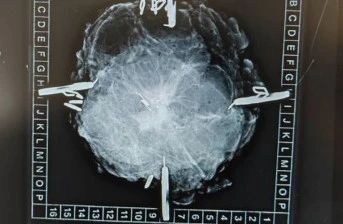

英国乳腺癌的手术保乳率相较国内高出不少,保乳手术和国内一样,确保手术切缘没有残留癌灶即为保乳成功。在患者手术前,会在需要切除的肿瘤区域中间放置mark,手术中使用探头进行探测,根据探测的数值高低决定手术切除的范围,切除后再次送检乳腺X线检查,查看mark的位置是否在手术区域中间,再送检病理,明确切缘情况。这种方法可以使手术更加精准,创伤更小。